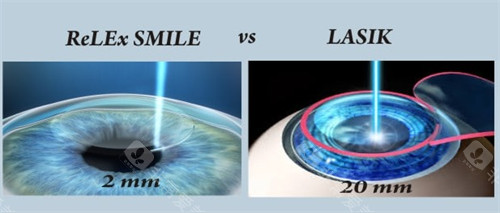

医院采用的手术方式主要有超声乳化白内障吸除术联合人工晶状体植入术等,这些手术方式具有切口小、改善快等优点。